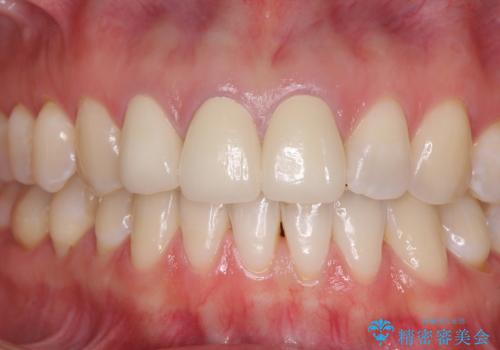

前歯は一部根管治療を行った後にオールセラミッククラウンに補綴することとしました。

補綴治療に先立ち、下顎前歯の部分矯正を行い、前歯の咬み合わせの安定性向上を図りました。

当初は上顎の補綴治療のみを希望されていましたが、仮歯装着期間に上下の前歯の接触が気になったため、部分矯正を行うこととしました。

審美面と合わせて機能面も改善され、患者様には大変満足していただきました。